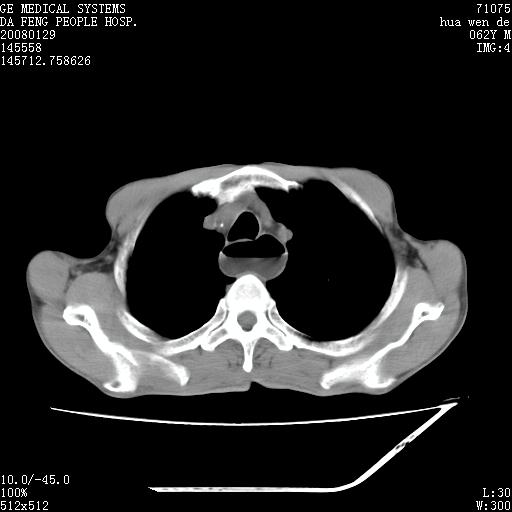

男性,67岁。作肺部检查时发现

右肺脓肿 胸腔胃

考虑1、右肺周围型肺癌可能性大。

2、贲门失迟缓症可能,建议钡餐检查。

考虑:胸腔胃并支气管瘘(并发肺炎,肺脓肿形成)。

理由:1、右上肺内病灶,空洞形成,有液平。

2、肺内多处炎症。

3、前段肺内炎症,支气管引流通畅,与肿块无关系。

1.整个食管扩张,未见明显占位性病变,贲门区亦未见明显占位病变,考虑:贲门失驰缓症;

2.右上肺病变边缘可见毛刺,囊壁厚度不均匀,周围境界较清楚,未见炎性渗出性影,右上肺外带可见片状影,边缘不清,考虑:肺癌伴空洞形成、右上肺炎。

食管全程扩张,壁均匀不厚,喷门失弛缓症

右上肺空洞可见液平,临近肺野磨玻璃密度,考虑1.结核2.脓肿